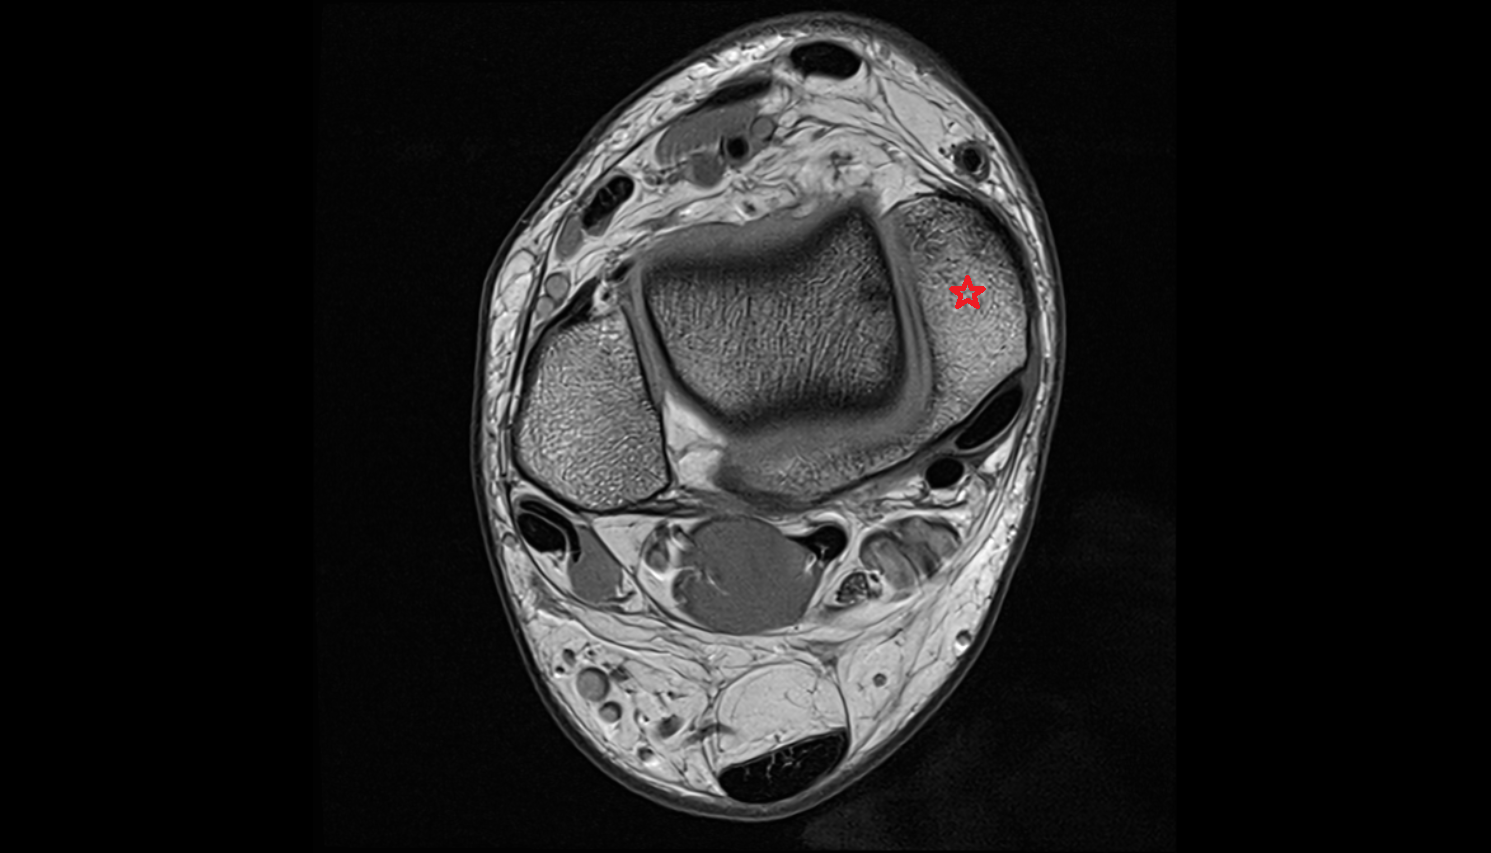

- Knee Joint